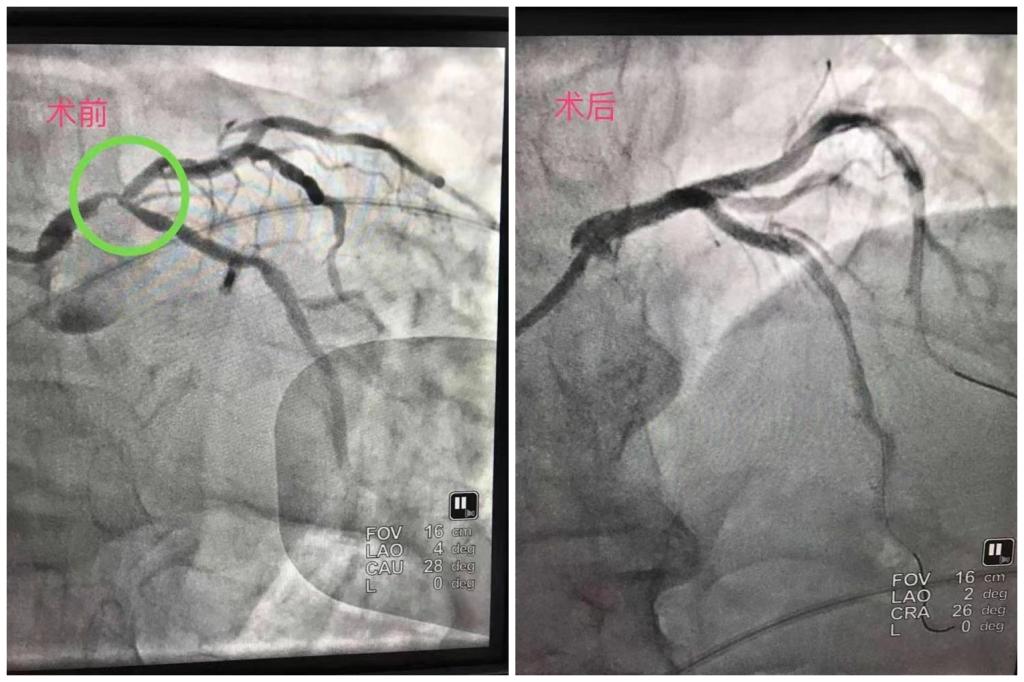

该病例记录的是一位老年男性,反复发生心绞痛,冠脉造影见左主干远端狭窄90%,回旋支开口及近端狭窄80%,前降支近端狭窄70%,右冠脉弥漫性狭窄50-80%。对于这种风险高,难度大的无保护左主干合并分叉病变及钙化重的病变,建议行冠脉搭桥术,但患者及家属愿承担风险,坚持要求冠脉介入微创治疗。在主动脉球囊反搏保护下,行裙裤(culottes)双支架术,并择期处理右冠脉病变。术后一年,复查冠脉造影见左主干、前降支、回旋支原支架通畅,无狭窄,心功能正常,患者恢复良好。